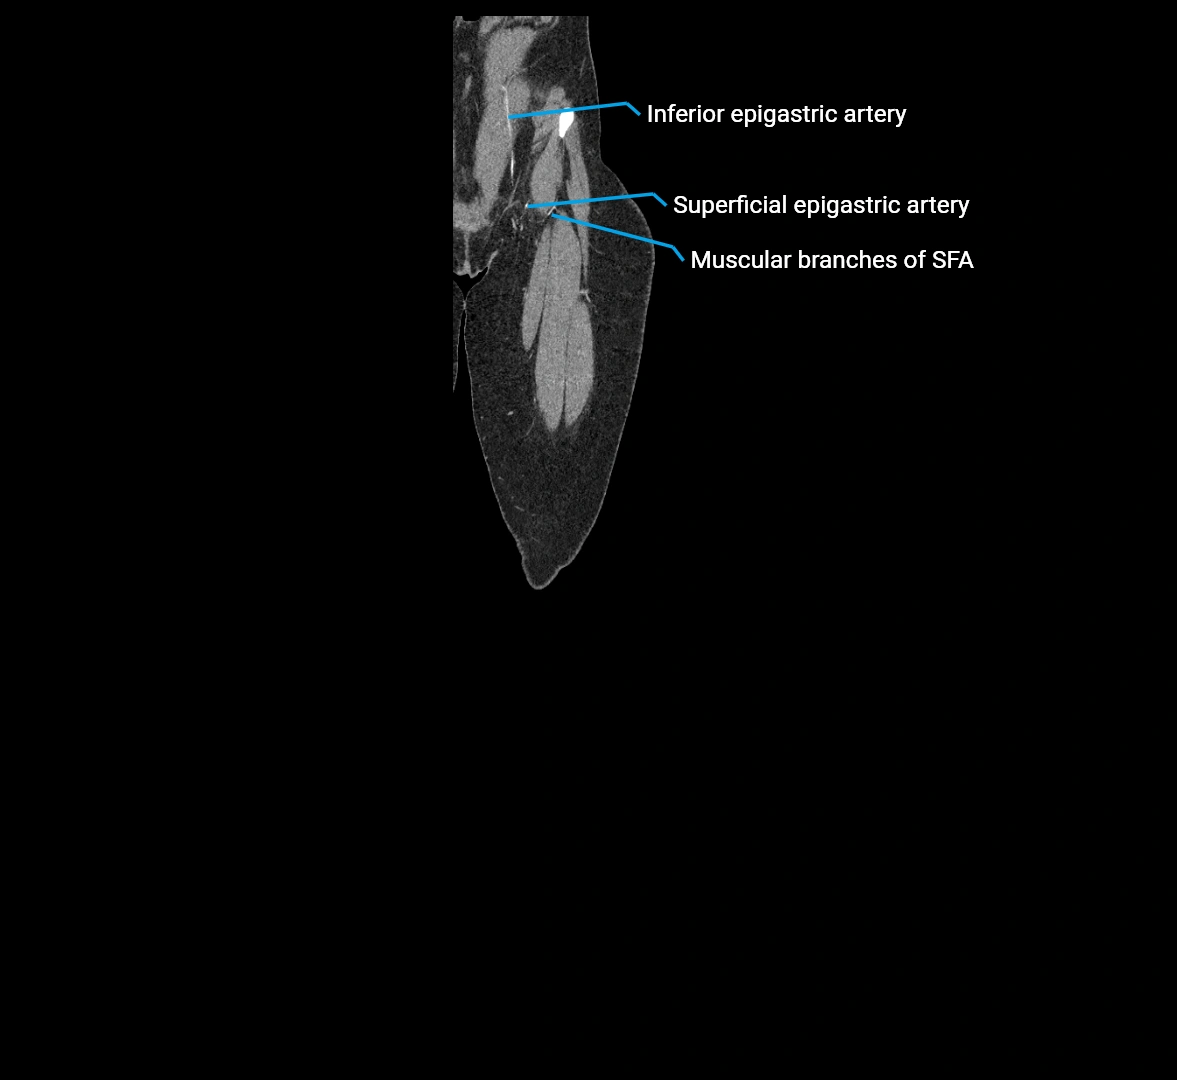

CT images

image